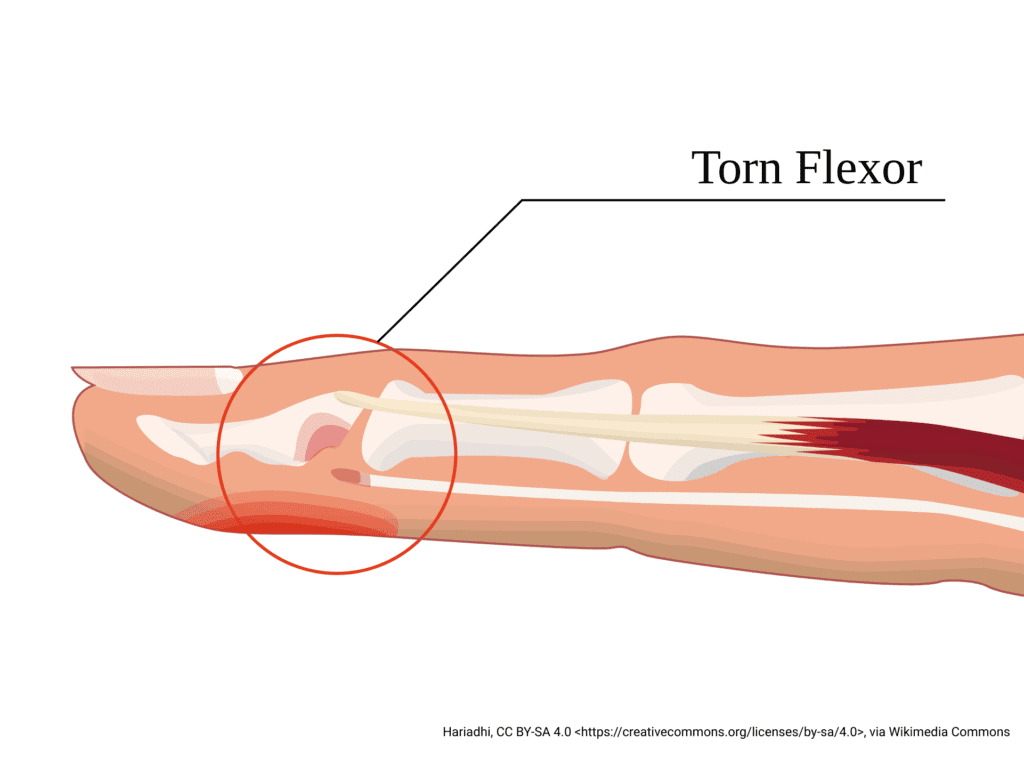

Jersey Finger

Jersey finger also often occurs during sports but is the opposite injury of mallet finger.

It happens when a finger is forcefully extended while the patient is trying to flex it. The classic example is grabbing another player’s jersey during a tackle.

Patients usually present with pain, swelling, and an inability to bend the tip of the finger.

This injury represents a rupture of the flexor digitorum profundus tendon.

Key exam finding: Inability to flex the DIP joint.

Unlike mallet finger, jersey finger almost always requires surgical repair. If the injury is missed, the tendon retracts and surgical repair becomes more difficult.

A simple exam maneuver helps identify this injury. Stabilize the middle phalanx and ask the patient to flex the tip of the finger. If they can’t, a flexor tendon injury should be suspected. Again, early orthopedic follow-up is key.